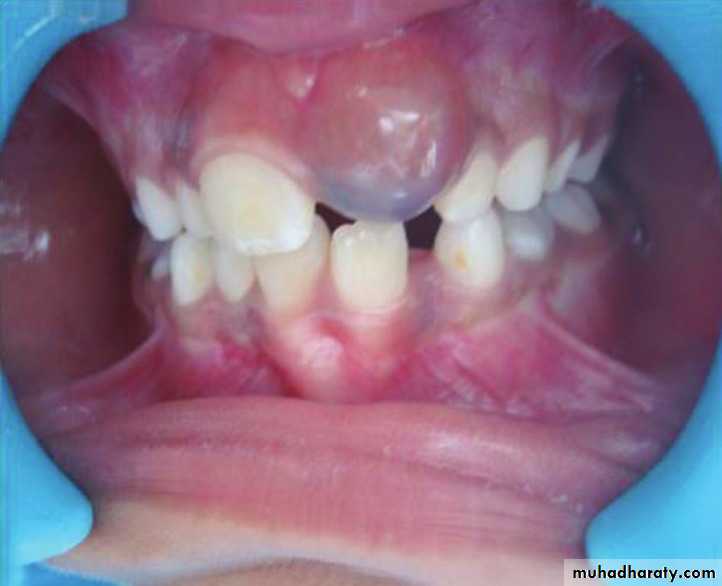

Eruption Cyst

The term eruption cyst is used to describe a dentigerous cyst when it is in the soft tissues overlying the unerupted tooth.• Odontogenic Fibroma